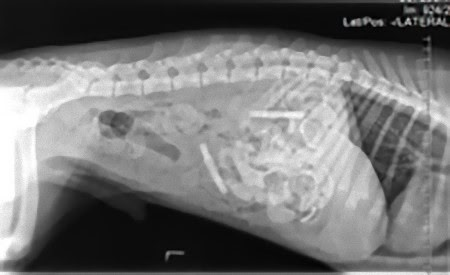

この画像を大きなサイズで見る準優勝写真:

12歳のビークル犬の体内に宿る、靴ひも、腐葉土、ストッキング、プラスチック、ネクタイと車用ブラシなど。